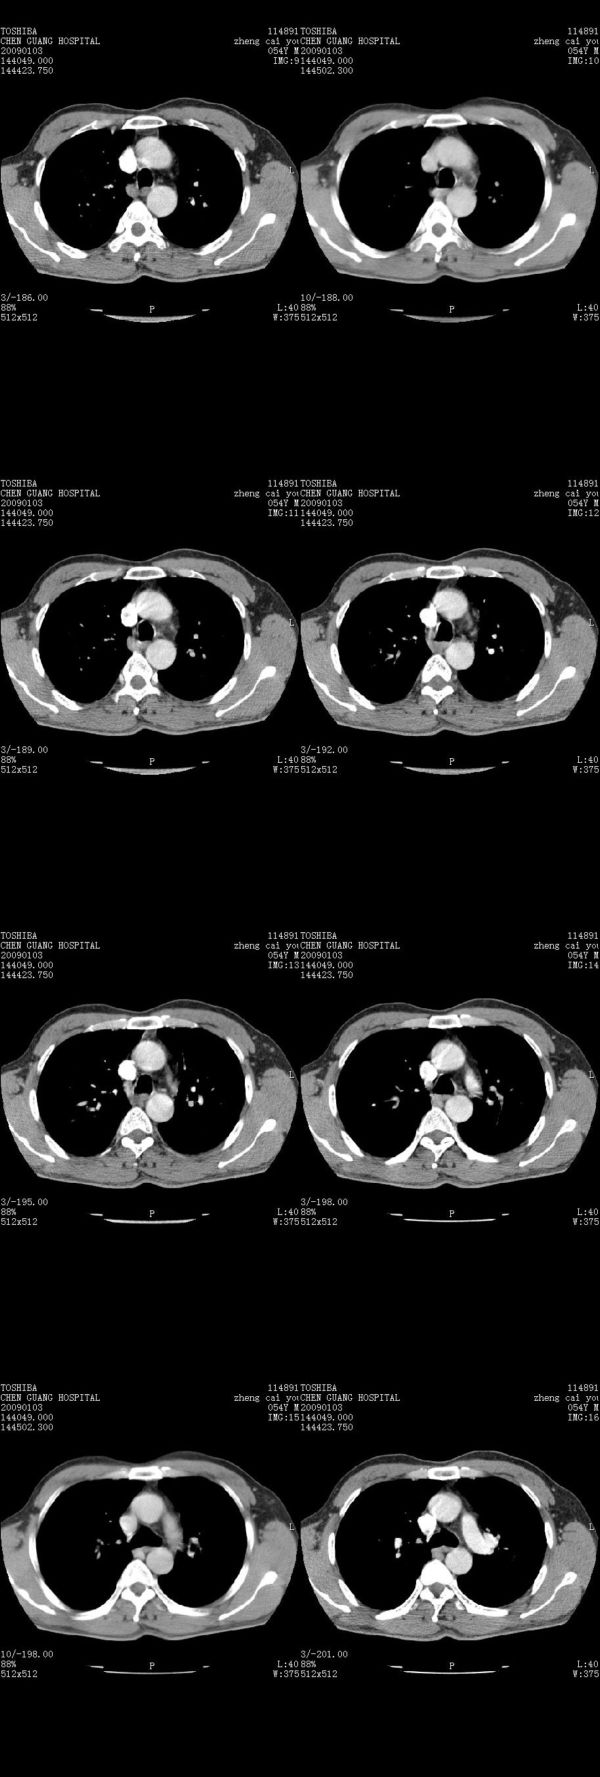

男,54岁,右侧胸部疼痛,平时吸烟,有抽烟后咳嗽咯痰史。昨天没把xiphoid软件吃懂,所以没把纵隔窗图像处理出来!请各位老师帮忙看一下右肺门有没有问题?谢谢!!!!!!!!!!

右肺上叶后段近气管旁仍可见一结节灶,不除外为肿大的淋巴结影。

我同学讲红线部分强化不好,感觉不是很舒服,这是什么道理?

我同学讲红线部分强化不好,感觉不是很舒服,应该 是软组织间隙,不是一个孤立的病灶。

气管前腔静脉后似见增大淋巴结影,肺门区未见明显肿块影。肺窗示右肺中叶外侧段透亮度增高,可过一段时间再查一下对比一下,毕竟是自己的至亲,又有条件,辐射就顾不得了。

也觉得还好吧,只是右下肺动脉显粗了点,纵膈有钙化淋巴结,再有肺窗就更好了

各位老师:奇静脉增宽,肺上未见明显实变,这还需注意观察些什么?????

右侧肺门影增大,不除外增大淋巴结可能

上腔静脉后淋巴结影,不知道最后结果怎么样?